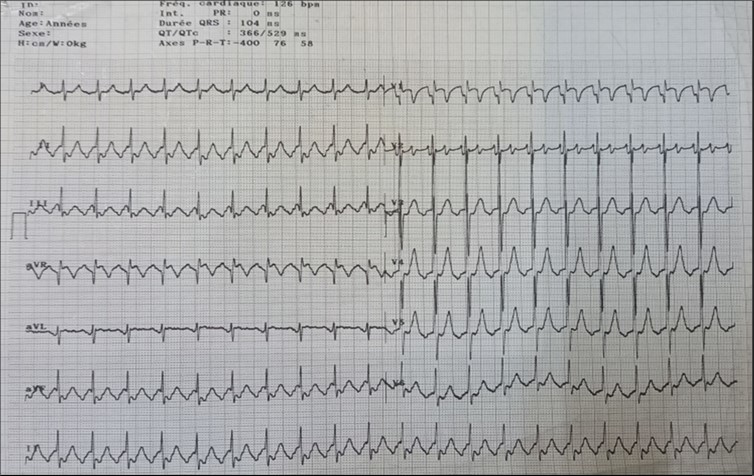

The frontal chest X-ray showed cardiomegaly with a cardiothoracic index of 0.7. The thoracic cavity and pulmonary parenchyma were without abnormality (Figure 1).

Figure 1.Frontal chest radiograph showing cardiomegaly

The EKG showed atrial flutter (Figure 2 ).

Cardiomegaly is frequent in Ebstein’s anomaly. A cardiothoracic ratio of at least 0.65 is associated with a poor prognosis 8 . This was the case with our patient.